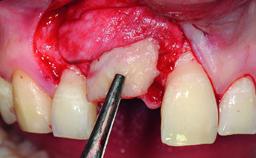

Replacement of an Ankylosed Upper Left Central Incisor: Bone Augmentation and Socket Grafting, Late Placement of an RC Bone Level Implant

Bone Augmentation Horizontal|Simultaneous|Staged

Augmentation Materials Autogenous chips|Xenogenous

Bone Volume Deficient horizontally, requiring prior grafting